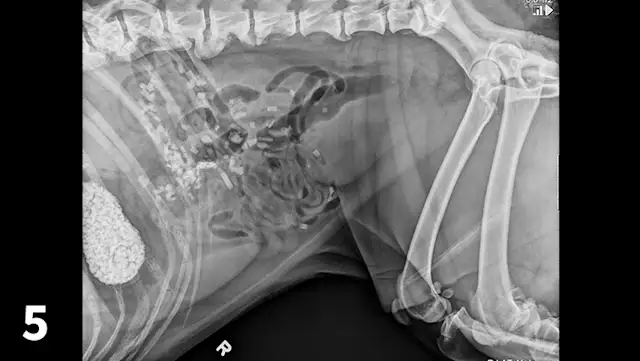

CBC reveals a leukocytosis (19.34 103/L; range, 5.10-14.00) characterized by a lymphocytosis (5.5 103/L; range, 1.4-4.6) and a mature neutrophilia (13.10 103/L; range, 2.65-9.80) with a mild thrombocytopenia (171 103/L; range, 147-243). A pancreatic-specific lipase is elevated (580 g/L; range, 0-200 g/L) and consistent with pancreatitis. Abdominal radiographs (Figures 1-3; See below) reveal a moderately distended stomach that contains a large number of irregularly shaped mineral opacities. Additional mineral opacities are present in multiple small intestinal segments as well as the colon. There is also a mild decrease in serosal detail in the mid-abdominal region.

A right lateral abdominal radiograph taken approximately 24 hours after glass ingestion. Multiple, irregularly shaped mineral opacities are present within the stomach, small intestine, and colon.